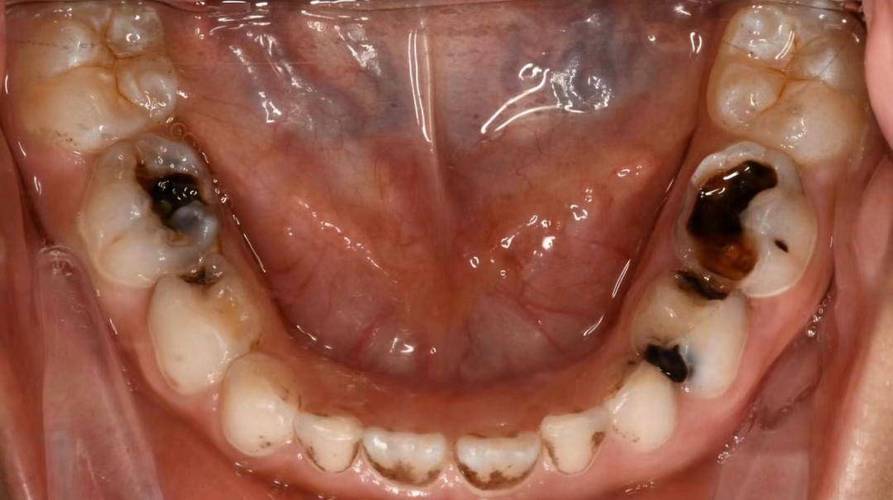

(图片来源网络,侵删)- 频繁进食甜食和零食:糖果、饼干、蛋糕、含糖饮料(果汁、乳酸菌饮料等)等,会为口腔细菌提供丰富的“养料”。